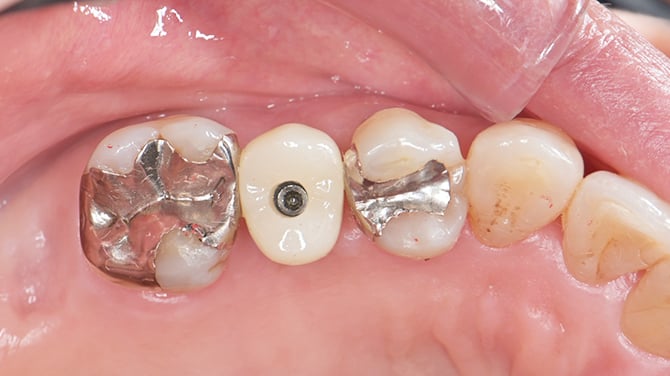

- 74歳女性の症例について

初診時74歳

主訴 主な症状は、歯がグラグラして痛むことなど

施術概要 レントゲン、CT、精密検査の結果、歯根破折が疑われるため、即時でインプラント埋入する計画が立てられました。

治療期間 約4ヶ月半

リスク・副作用 歯根破折に伴う感染をしっかり除去できれば大きなリスクはないと判断

治療結果 治療後3か月で2次オペを行い治療が終了しました。